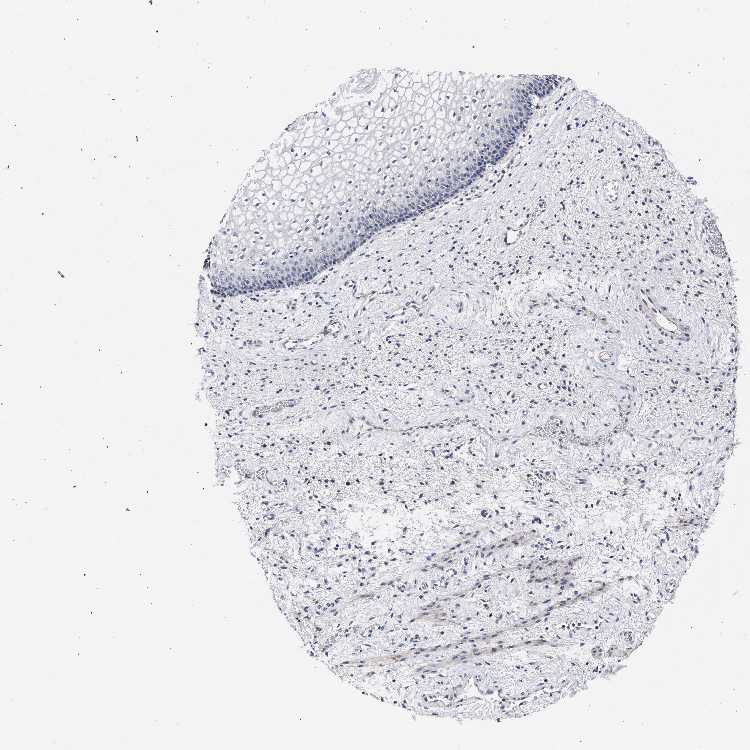

VAGINA - Antibody stainingi

Antibody staining in the annotated cell types in the current human tissue is reported as not detected, low, medium, or high, based on conventional immunohistochemistry profiling in selected tissues. This score is based on the combination of the staining intensity and fraction of stained cells.

Each image is clickable and will lead to virtual microscopy that enables deeper exploration of all samples and also displays staining intensity scores, fraction scores and subcellular localization as well as patient and tissue information for each sample.

Antibody HPA021261Antibody HPA021325

Squamous epithelial cells Not detectedNot detected